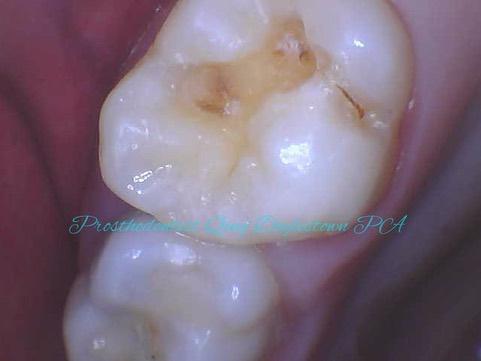

Tooth decay undermines tooth structure, symptoms are often not obvious until a later stage, similar to Periodontitis. Figure 1 shows some shadow on the intact tooth surfaces, until it is opened up to find out how much decay was underneath.